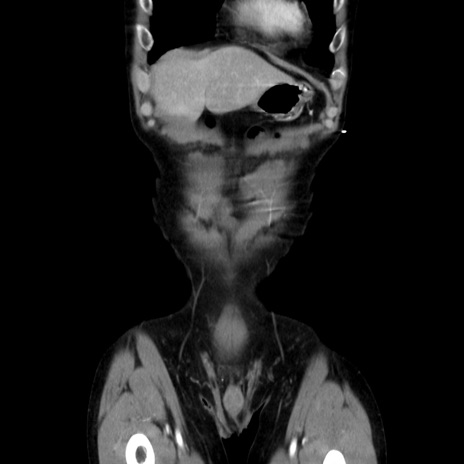

症例37(冠状断像)

横断像